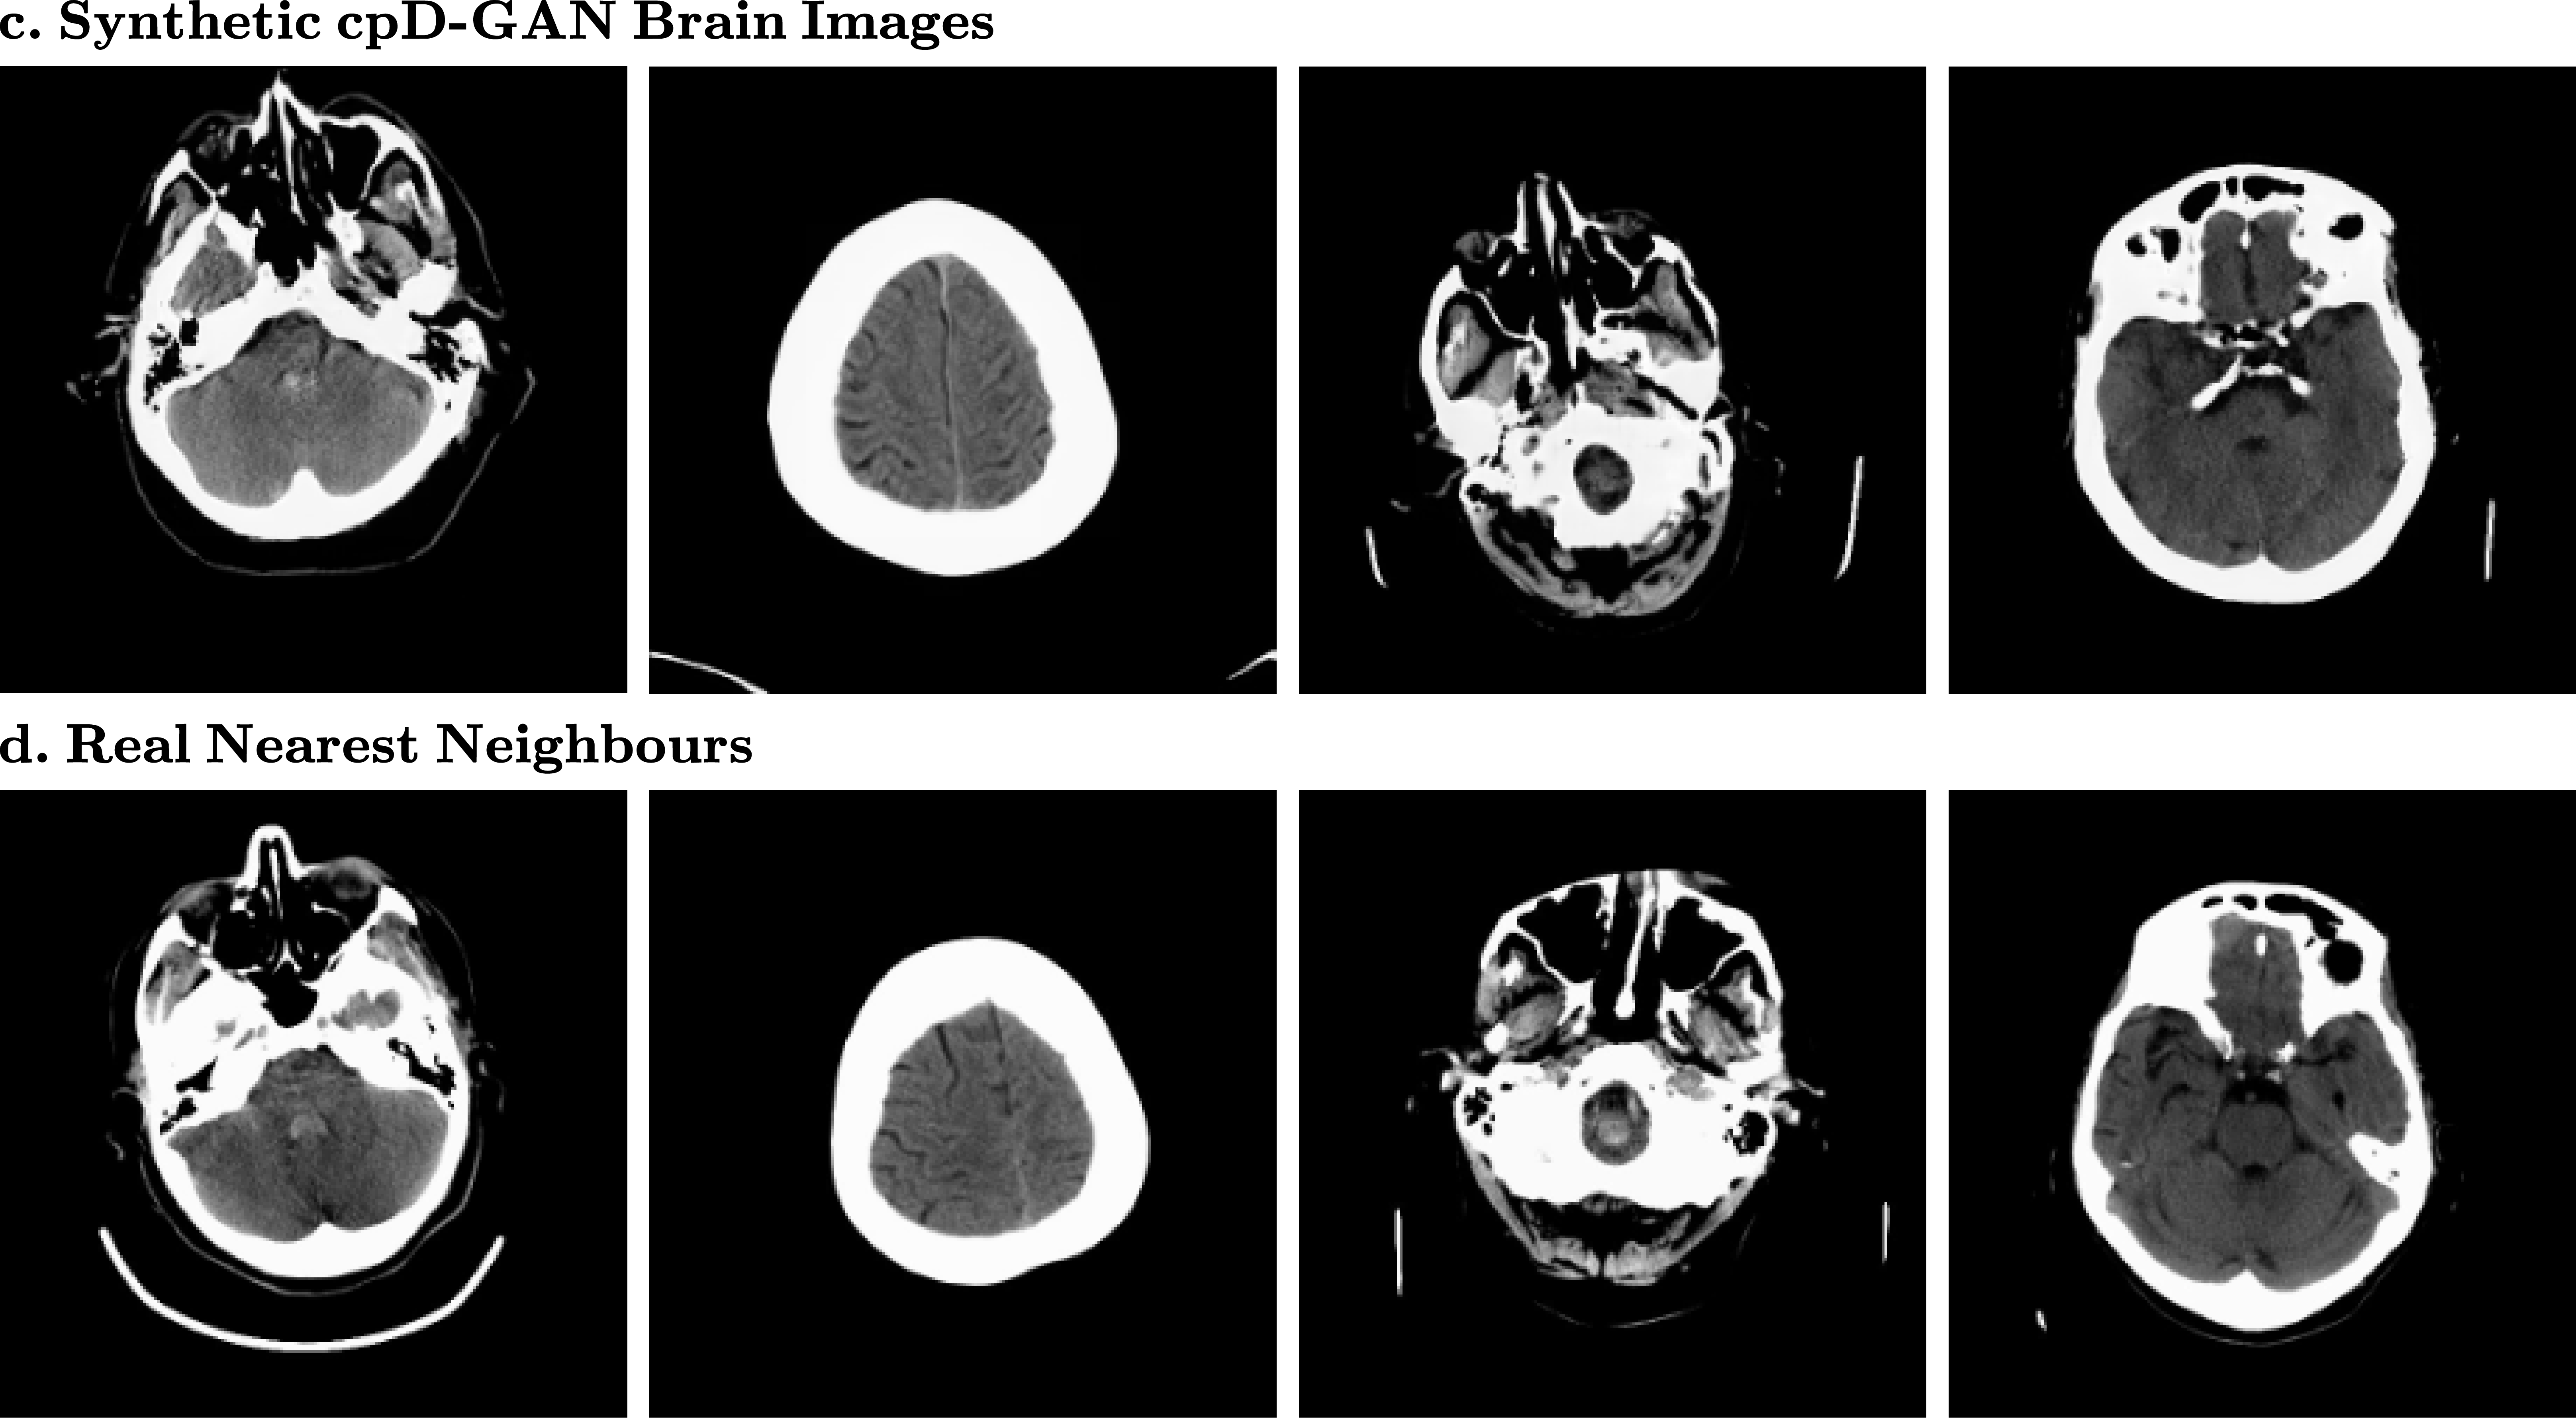

Figure 2:

(c.) Synthetic brain CT scans and (d.) closest matching real nearest neighbours at a resolution of 256 x 256 pixels

In Fig. 2 we show some randomly sampled synthetic example images at a resolution of 256 x 256 pixels for the brain CT scans. There appears to be little noticeable difference in visual quality between the real and synthetic images, which is in agreement with a close-to-random classification accuracy of trained radiologists in the reader study. Below each synthetic image, you can see the most similar real image out of the entire training dataset. By comparing synthetics and nearest matching neighbours we can observe that the GAN model did not simply memorise training data, and is therefore likely to preserve private, potentially sensitive information.